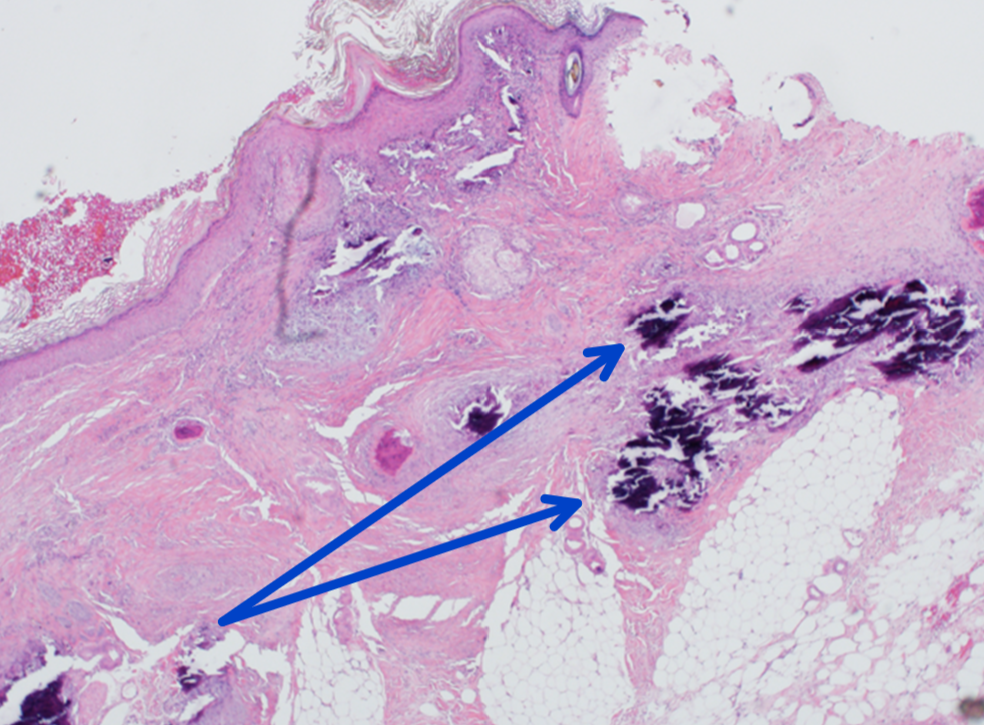

Q

there are multifocal, white to tan, firm plaques within the epidermis/dermis on the dorsal aspect of the neck. On cut surface the plaques are firm and gritty. The plaques are diffusely pale in color

15

Provide a morphological diagnosis for this lesion.

Skin: chronic, multifocal to coalescing, dermal calcificaiton

16

What is this basophilic material?

mineral

17

A large number of macrophages, epithelioid macrophages, and multinucleated giant cells surround the foci. What would be a good morphologic diagnosis considering the inflammation?

chronic granulomatous dermatitis with dystrophic mineralization

18

How does chronic use of prednisone in this patient relate to the gross findings?

Chronic administration of prednisone can cause iatrogenic Cushing’s (hyperadrenocortisim) disease. Hyperadrenocortism can cause dermal atrophy/ thinning and mineralization.

19

Will this lesion resolve after discontinuing the prednisone treatment?

The lesions can resolve if the prednisone is stopped. It could take a while for the mineral to be reabsorbed. The mineral might never be removed if there is extensive dermal fibrosis.